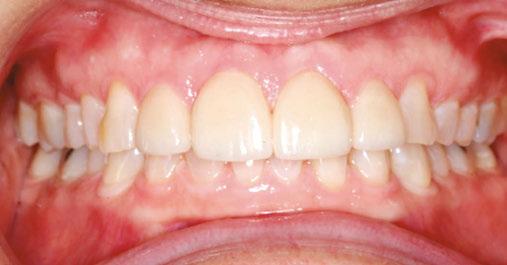

A 49-year-old female presented for an initial orthodontic exam with the chief complaint of bruxing and excessive wear on her teeth, especially the anterior. She was aware of the loss of tooth height and discussed restoration plans with her dentist. She had no history of previous orthodontic treatment and was wearing a maxillary flat-plane occlusal guard from her dentist. She was aware of daytime clenching and grinding but did not report any TMJ pain, clicking, or popping. Maximum opening and range of motion were within normal limits. Cephalometric

Figures 1-5: Initial dental photos

analysis showed that she had a brachycephalic skeletal pattern, but ANB and inter-incisal angles were normal. Occlusal wear in and of itself does not affect patient quality of life,3 but some patients are self-conscious about the appearance of their short, worn teeth, which is the category that this patient fits into. Her chief concern was to improve her dental esthetics.

With the anterior tooth wear, she had lost a few millimeters from the incisal edges of her teeth, which had super-erupted to maintain contact with the lower anterior teeth. The patient had a gingival height discrepancy with teeth Nos. 6-11 due to the wear and subsequent super-eruption. She had also lost tooth structure from the incisal edges on teeth Nos. 23-26 but did not want to restore the lower anterior teeth post-orthodontic treatment. Her general dentist planned on restoring teeth Nos. 7, 8, 9, and 10 with veneers or crowns.

The orthodontic treatment plan was to bond upper and lower Ormco Symetri brackets (bidimensional prescription) and intrude teeth Nos. 7-10 along with lower anterior (teeth Nos. 23-26) to establish better overbite and overjet for restorative work. Due to the loss of height of her anterior teeth, the interproximal contacts had also moved gingivally, which decreased the width of the anterior teeth (height-to-width ratios were off). In order to establish better crown ratios, the

plan was to open space mesial and distal to teeth Nos. 7-10 with open coil springs.

Though she had a rather deep bite, the Ormco Symetri bracket was low-profile and petite enough to bond the entire upper and lower braces the same day. She had no occlusal interferences with the brackets, and bite turbos were not required. The Symetri bracket’s rounded contours were comfortable to the patient, and she liked that the brackets blended with her tooth shade and met her esthetic requirements. She reported adjusting to the braces easily. The initial wires were light, 0.014 nickel-titanium archwires, and we gradually progressed into rectangular, 0.16 x 0.22 stainless steel wires for finishing. Coils were added mesial and distal to teeth Nos. 7-10 to improve the width-tolength ratios of the crowns, and teeth Nos. 7-10 were stepped up gradually to intrude them. Ideally, gingival margins of teeth Nos. 8 and 9 should be at the level of tooth No. 6 and 11, while teeth Nos. 7 and 10 should be about 1.5 mm lower5 than the centrals. As the maxillary anterior teeth were intruded, and spaces were introduced mesial and distal, the incisal angulation of the teeth also increased. This can be protective for people with a history of bruxing, in addition to leaving more inter-incisal clearance for the restoring dentist.

This case was completed in 14 months and likely would have been completed sooner if not for her occasional broken archwires. She was delighted with the esthetics and comfort of her clear brackets and is happy with her esthetic result. The Ormco Symetri Clear bracket system helps to increase case acceptance while giving the orthodontist the control and predictability required to finish complex restorative cases efficiently.